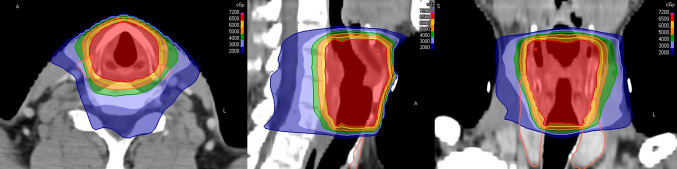

Abstract Image